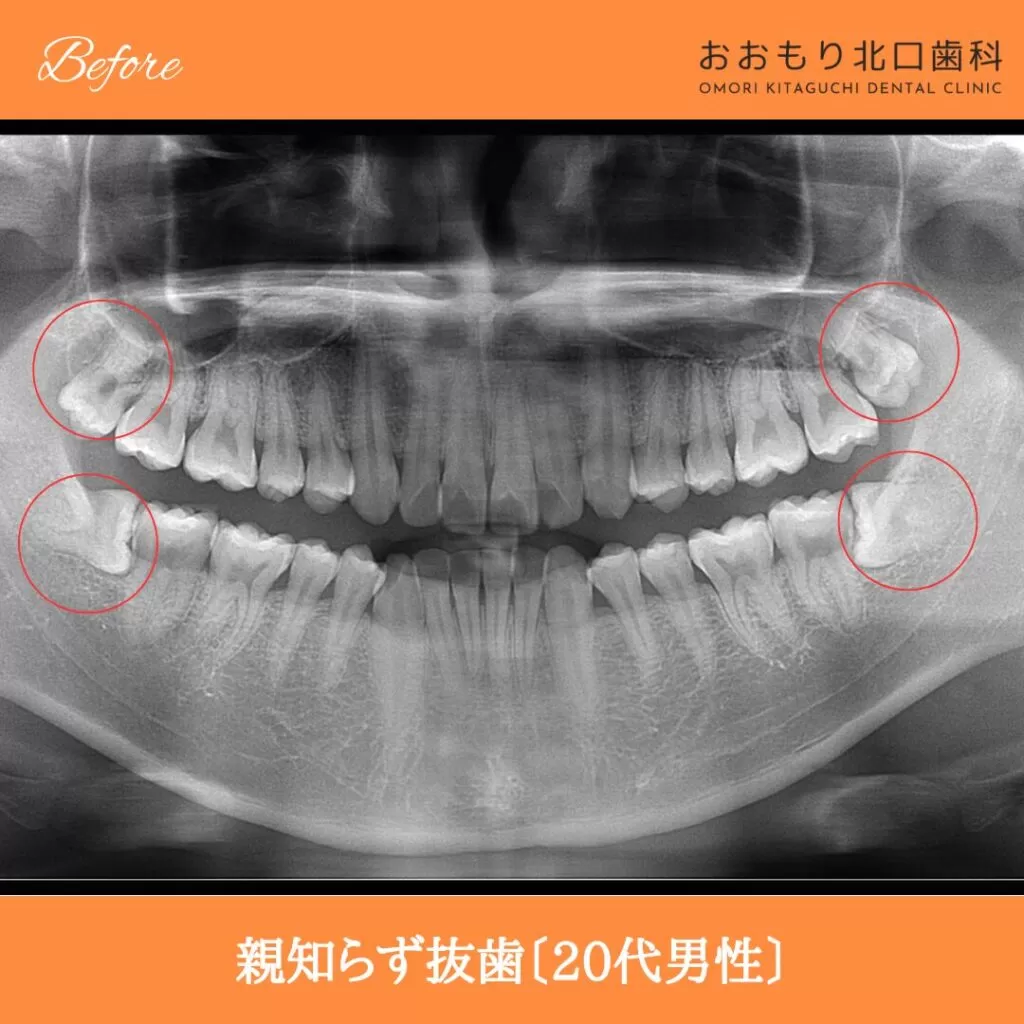

症例紹介㊸親知らず抜歯(20代男性)

【治療名】親知らず抜歯

【患者さん】20代男性

【費用(税込)】保険治療

【リスク】 親知らずの抜歯は、手術中は麻酔により痛みを感じることがほとんどありません。

しかし、麻酔が切れた後には、時には腫れや痛みが発生することがあります。